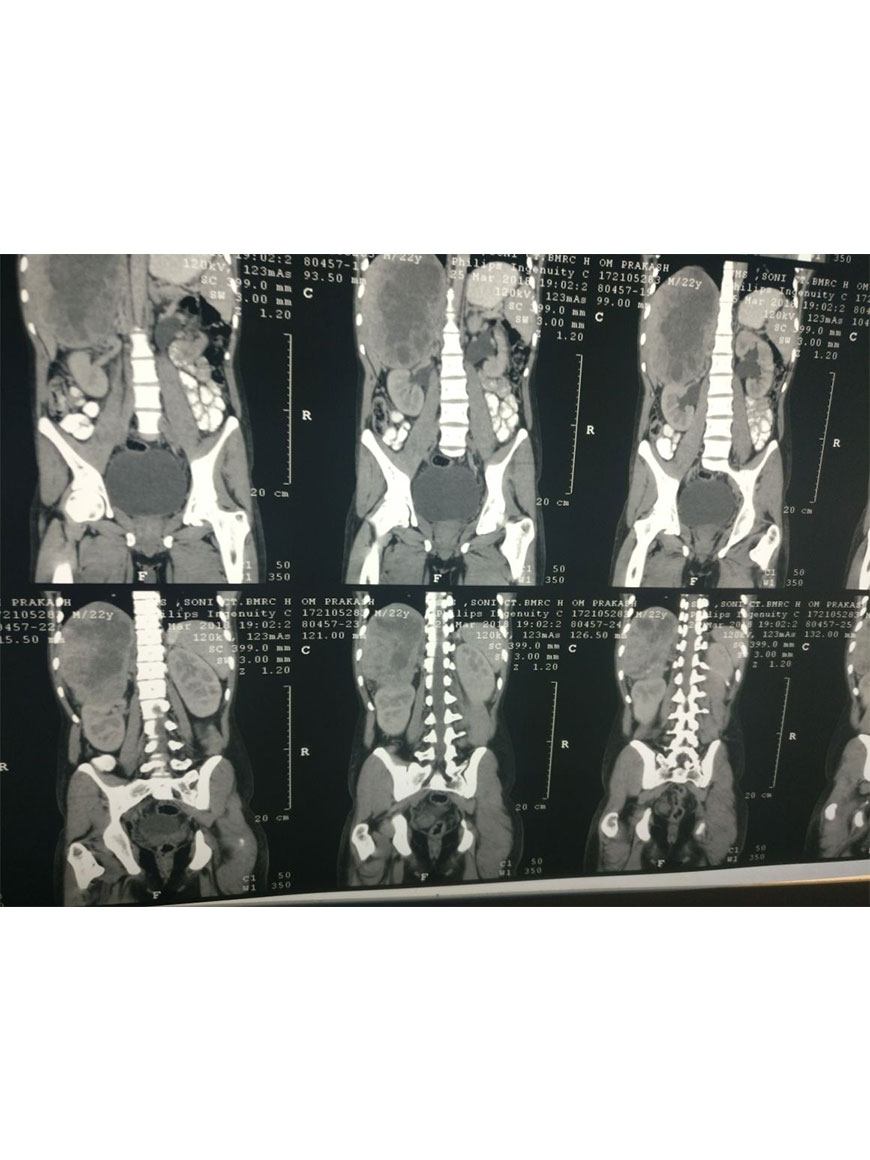

Radical Nephrectomy